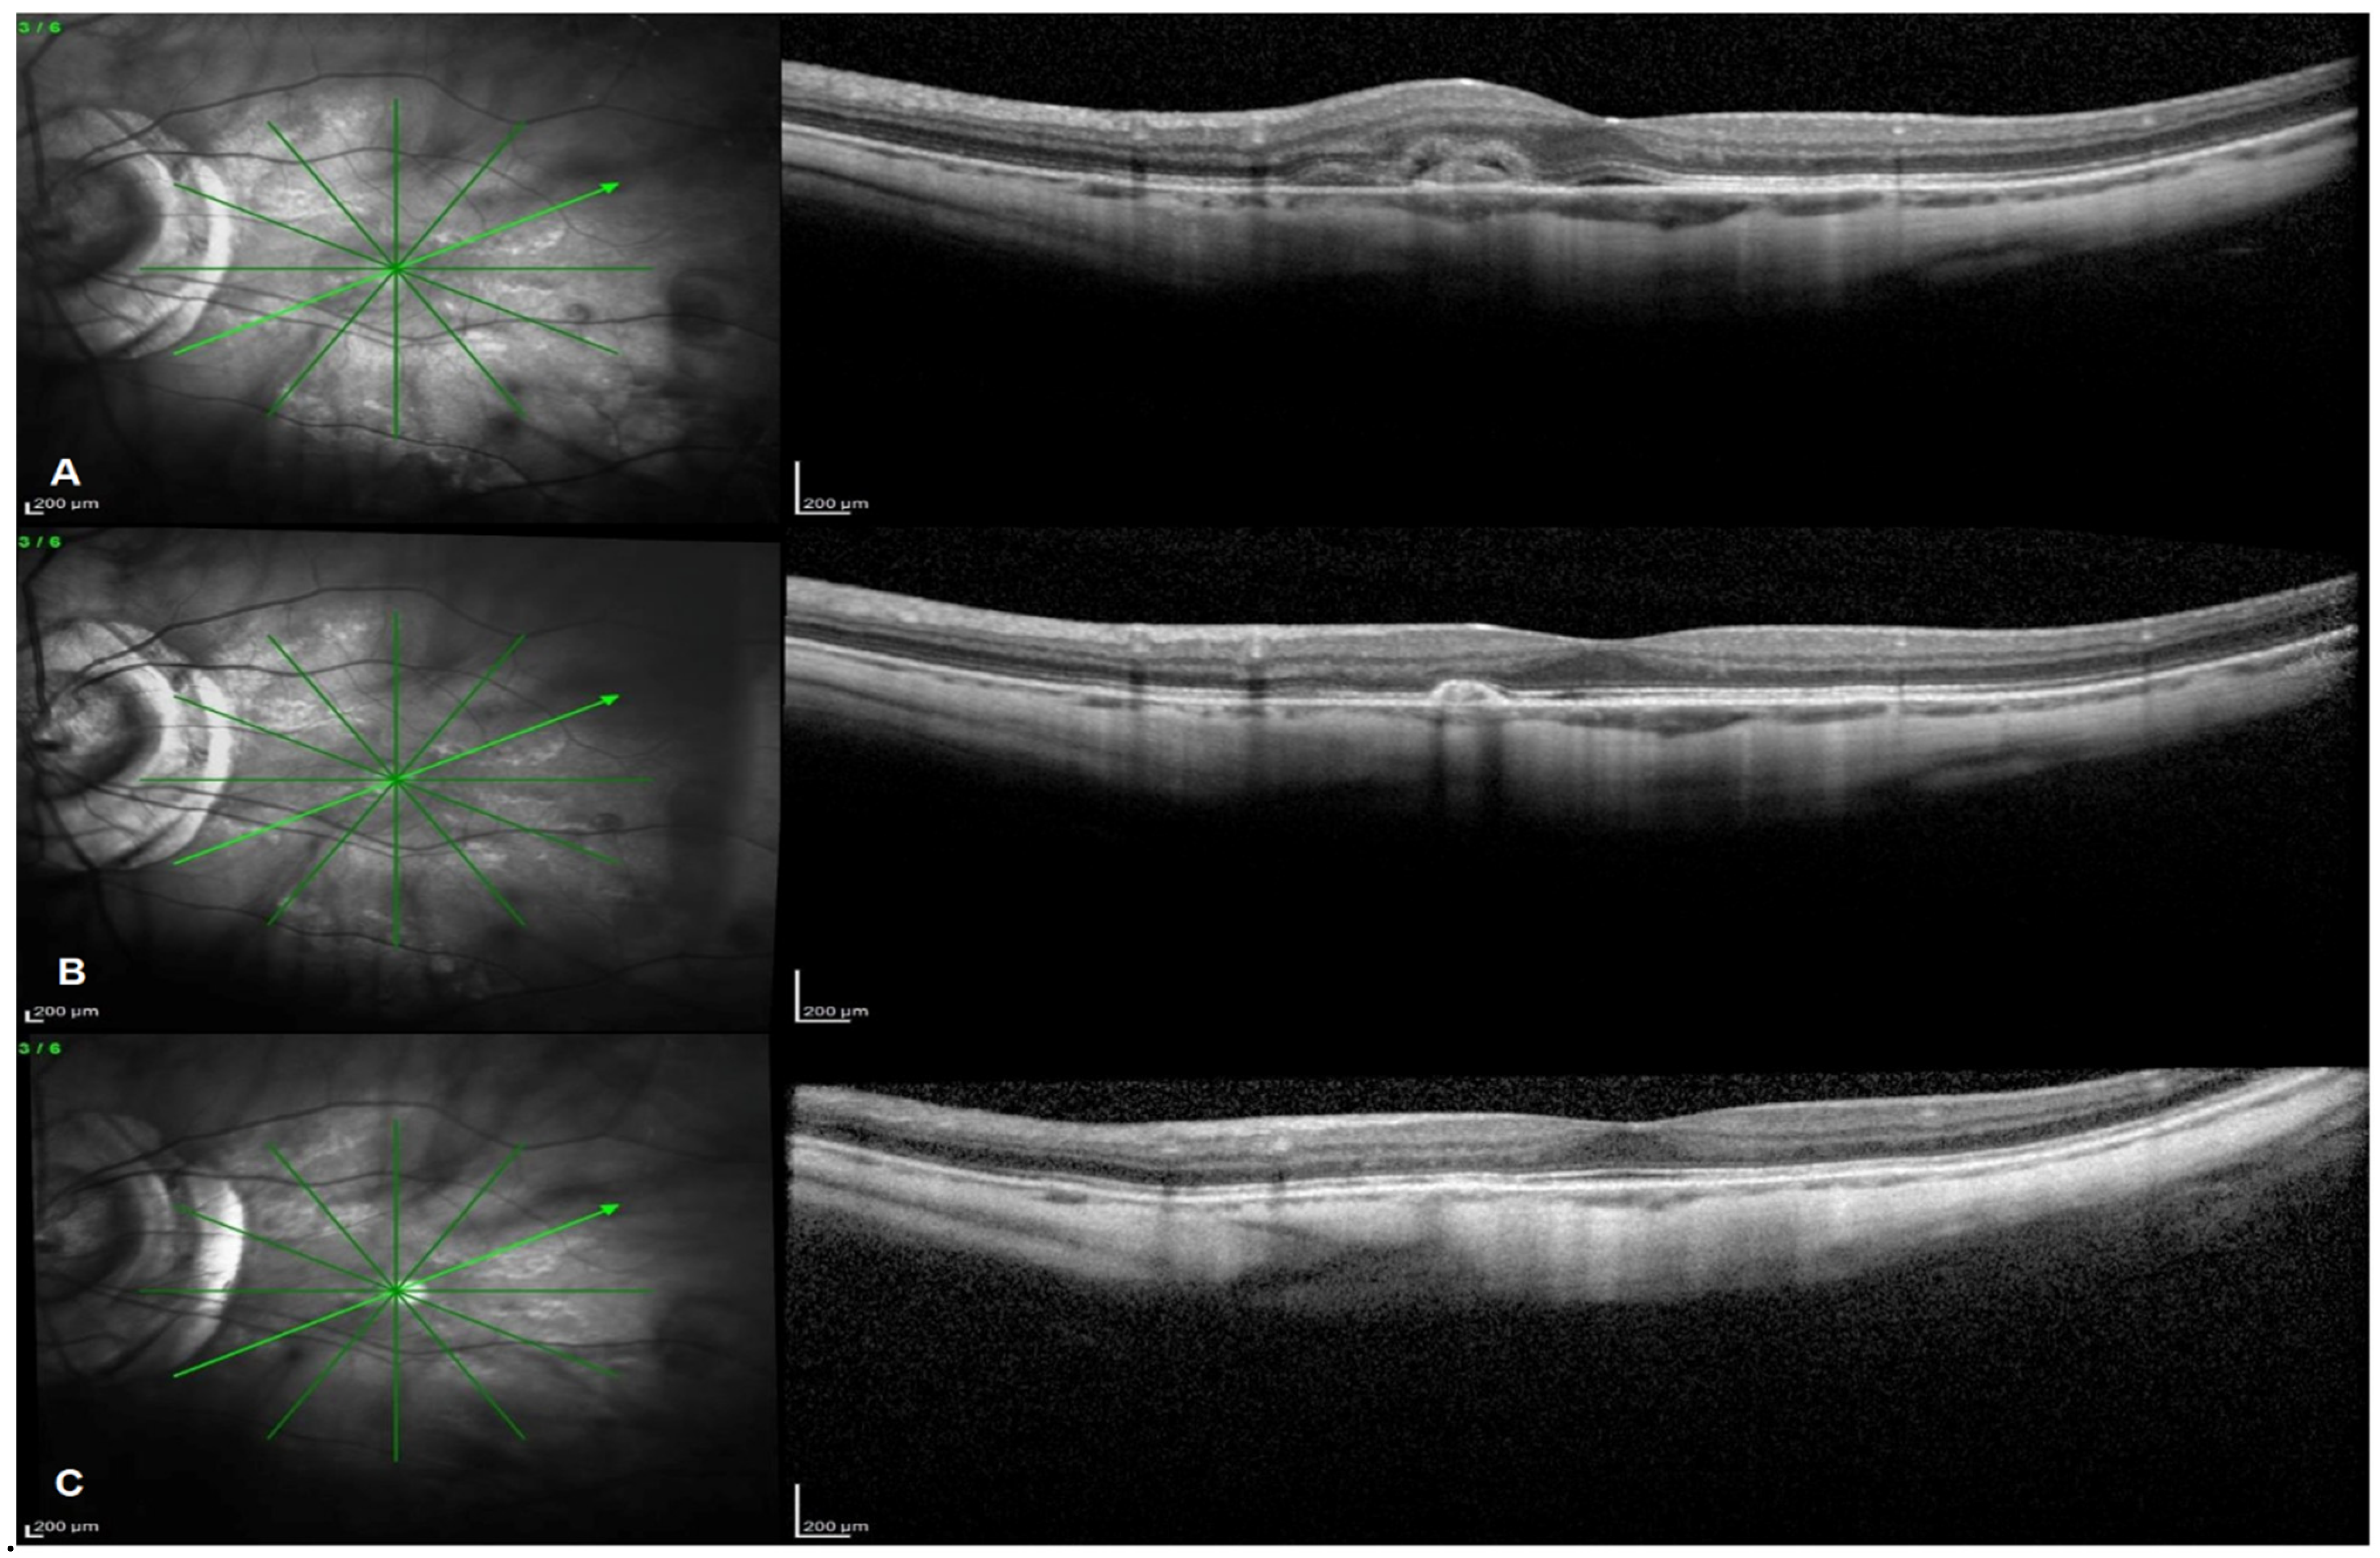

2.3. OCT and FA Outcomes